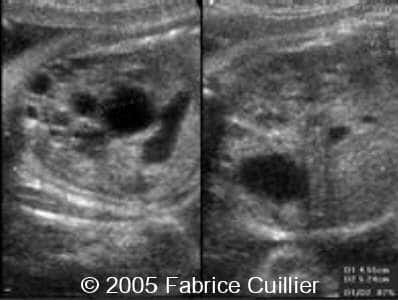

Multicystic kidney disease, unilateral

These are serial scans in a case of unilateral multicystic kidney disease.

Scan at 29 weeks of gestation:

Scan at 31 weeks of gestation: